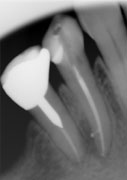

それに加え、根の消毒に使う薬剤にもこだわり、最新の薬剤を使用しています。清掃した根を緊密に詰める方法も大学では既成のゴム栓に接着剤をつけて根を詰めていましたが、枝分かれした根には詰められませんでした。したがって、現在は当医院では、生体に親和性の高い純度の高いガッタパーチャというゴムを軟化して、加圧して根を詰めています。この方法は非常に高い技術が必要ですが、写真のように(図4〜11)非常に良い結果を残しています。

図4